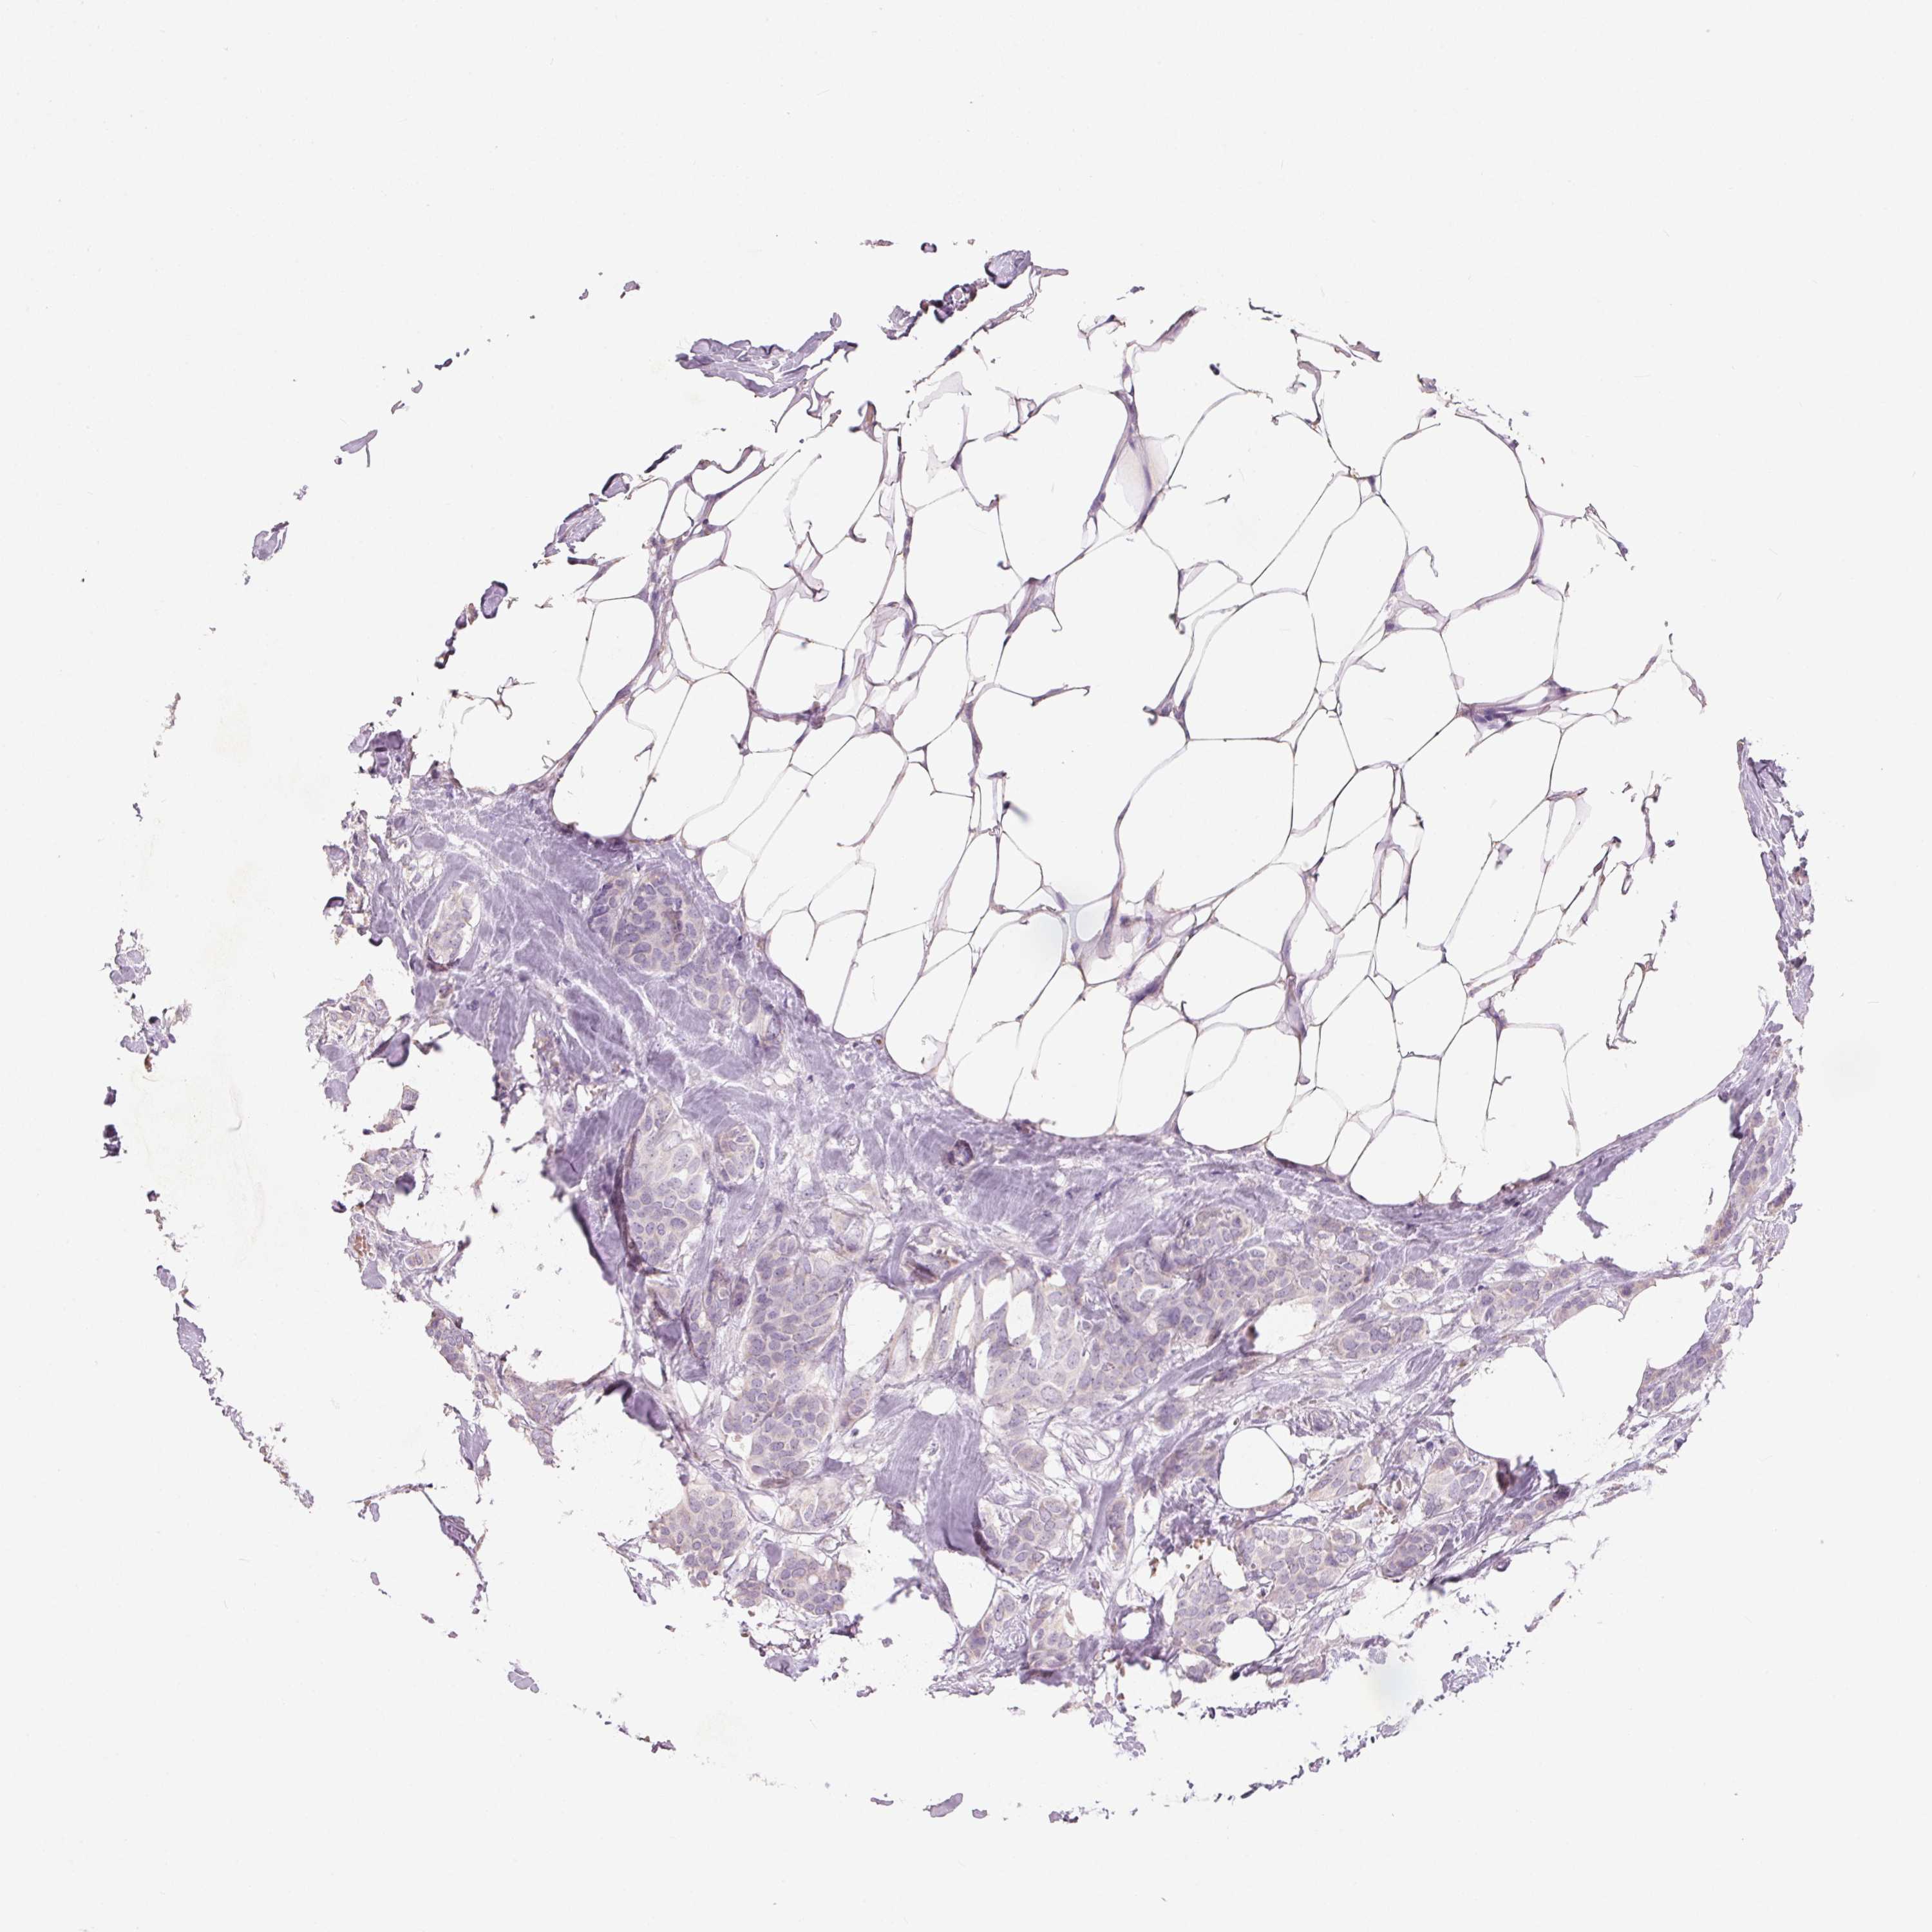

Breast cancer

Human cancer